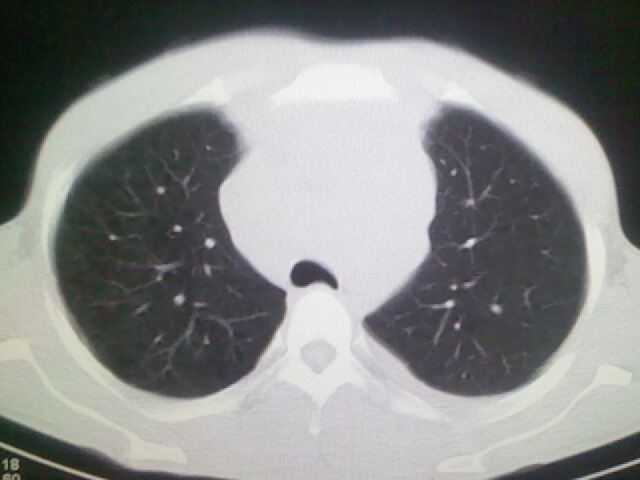

以下是引用杀毒软件在2008-9-3 6:11:00的发言:[br]侵袭性胸腺瘤------一般不侵到气管旁[br][br]考虑----纵隔淋巴瘤,心包及胸膜受累

以下是引用随光逐影在2008-9-3 7:07:00的发言:[br]1)考虑淋巴瘤可能。2)双侧胸腔积液(以左侧为甚)。3)心包积液。